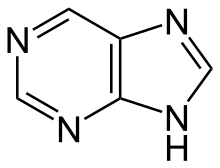

Purine derivatives[139]

|

Xanthosine (formed in purine biosynthesis) → 7 methylxantosine → 7-methylxanthine → theobromine → caffeine[85] | Caffeine, theobromine, theophylline, saxitoxin[140][141] | |